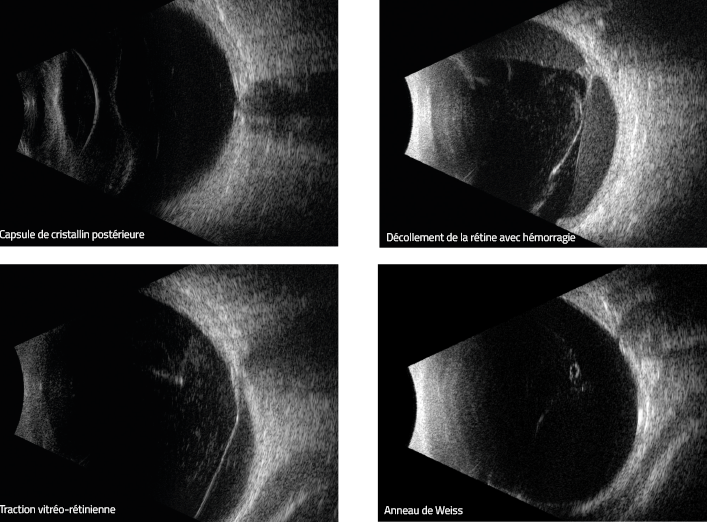

Echographie oculaire mode B

Examen à l'aide d'ultrasons permettant d'examiner la partie postérieure de l'œil et ses structures internes : vitré, sclère, choroïde, rétine, papille, macula.